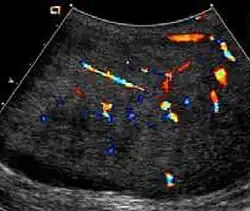

Patients with testicular lymphoma are usually old aged around 60 years of age, present with painless testicular enlargement and less commonly with other systemic symptoms such as weight loss, anorexia, fever and weakness. Bilateral testicle involvements are common and occur in 8.5% to 18% of cases. At sonography, most lymphomas are homogeneous and diffusely replace the testis [Fig. 7]. However focal hypoechoic lesions can occur, hemorrhage and necrosis are rare. At times, the sonographic appearance of lymphoma is indistinguishable from that of the germ cell tumors [Fig. 8], then the patient's age at presentation, symptoms, and medical history, as well as multiplicity and bilaterality of the lesions, are all important factors in making the appropriate diagnosis.

At ultrasound, the findings of acute epididymitis include an enlarged hypoechoic or hyperechoic (presumably secondary to hemorrhage) epididymis [Fig. 20a]. Other signs of inflammation such as increased vascularity, reactive hydrocele, pyocele and scrotal wall thickening may also be present. Testicular involvement is confirmed by the presence of testicular enlargement and an inhomogeneous echotexture. Hypervascularity on color Doppler images [Fig. 20b] is a well-established diagnostic criterion and may be the only imaging finding of epididymo-orchitis in some men.